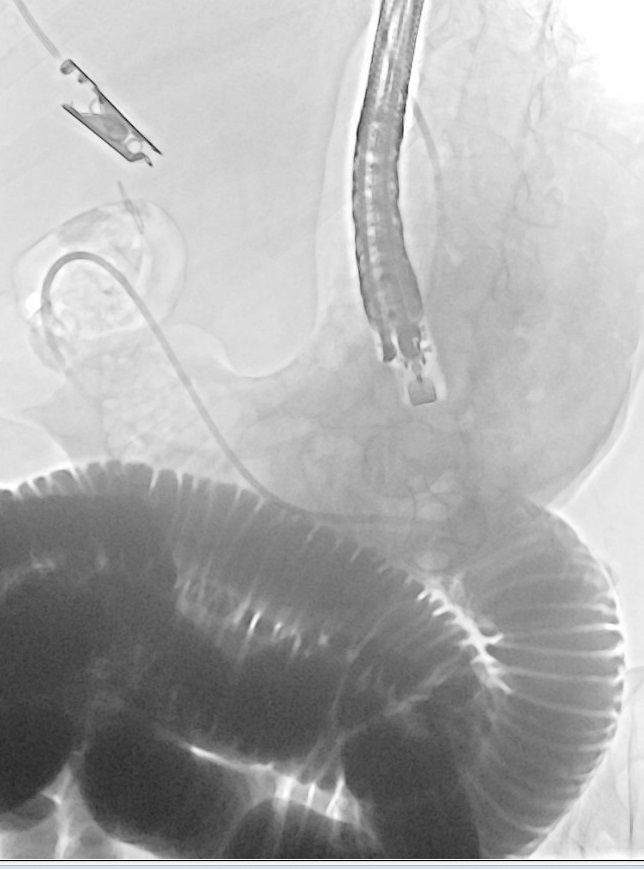

@DouglasAdlerMD

Douglas G. Adler MD, FASGE, FACG, AGAF

3 days

Now THAT is a big common bile duct stone! #gitwitter #surgery @Stentingwoman @EUSandEndoscopy @DavidDiehlMD